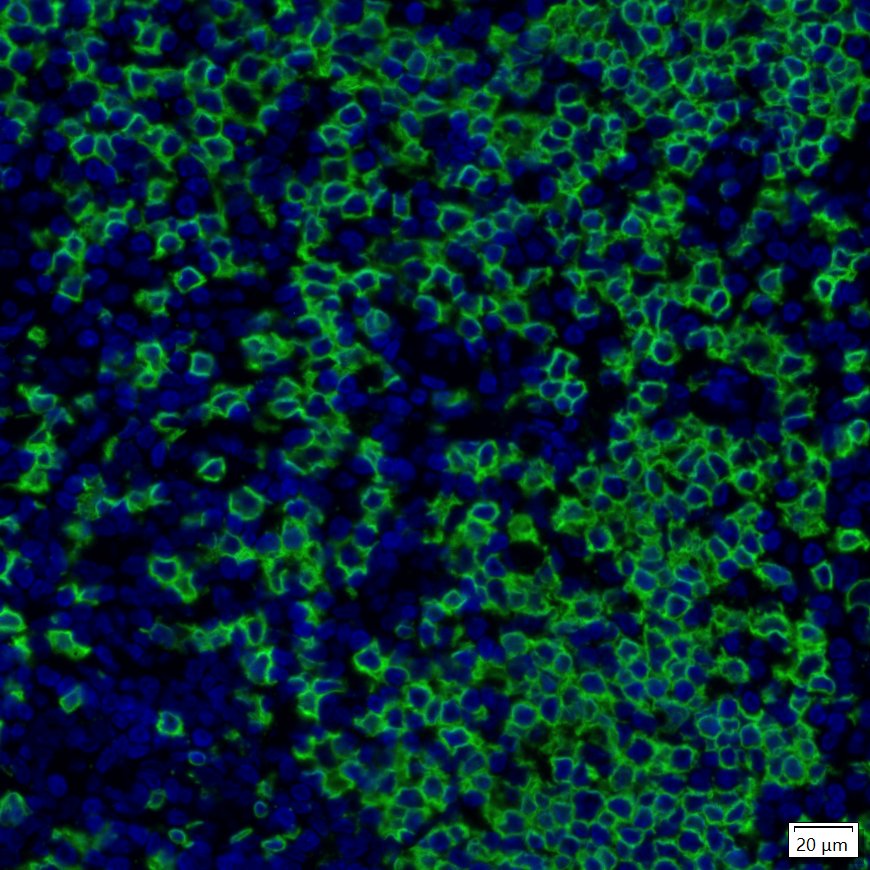

IRS003_10.jpg Fig10: mIHC analysis of human tonsil tissue (Formalin/PFA-fixed paraffin-embedded sections) with Rabbit anti-CD20 antibody (IRS003) at 1/100 dilution. The immunostaining was performed with the IRISKitCmTSA Kit (900808). Heat mediated antigen retrieval with Tris-EDTA buffer (pH 9.0) for 30 mins at 95℃. DAPI (blue) was used as a nuclear counter stain. Image acquisition was performed with Olympus VS200 Slide Scanner.